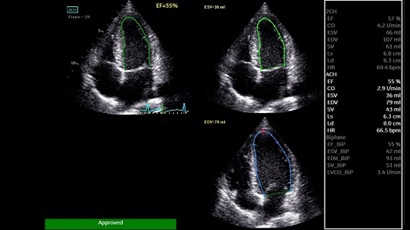

AUTO 2D EF:

Да

• AUTO 2D EF - режим автоматической недопплеровской количественной оценки глобальной сократительной функции ЛЖ (по Simpson).

• AFI - режим цифровой недопплеровской качественной и количественной оценки региональной сократительной функции ЛЖ.

• 4D AUTO LVQ - модуль расчета массы миокарда ЛЖ на основе данных 4D-исследования.